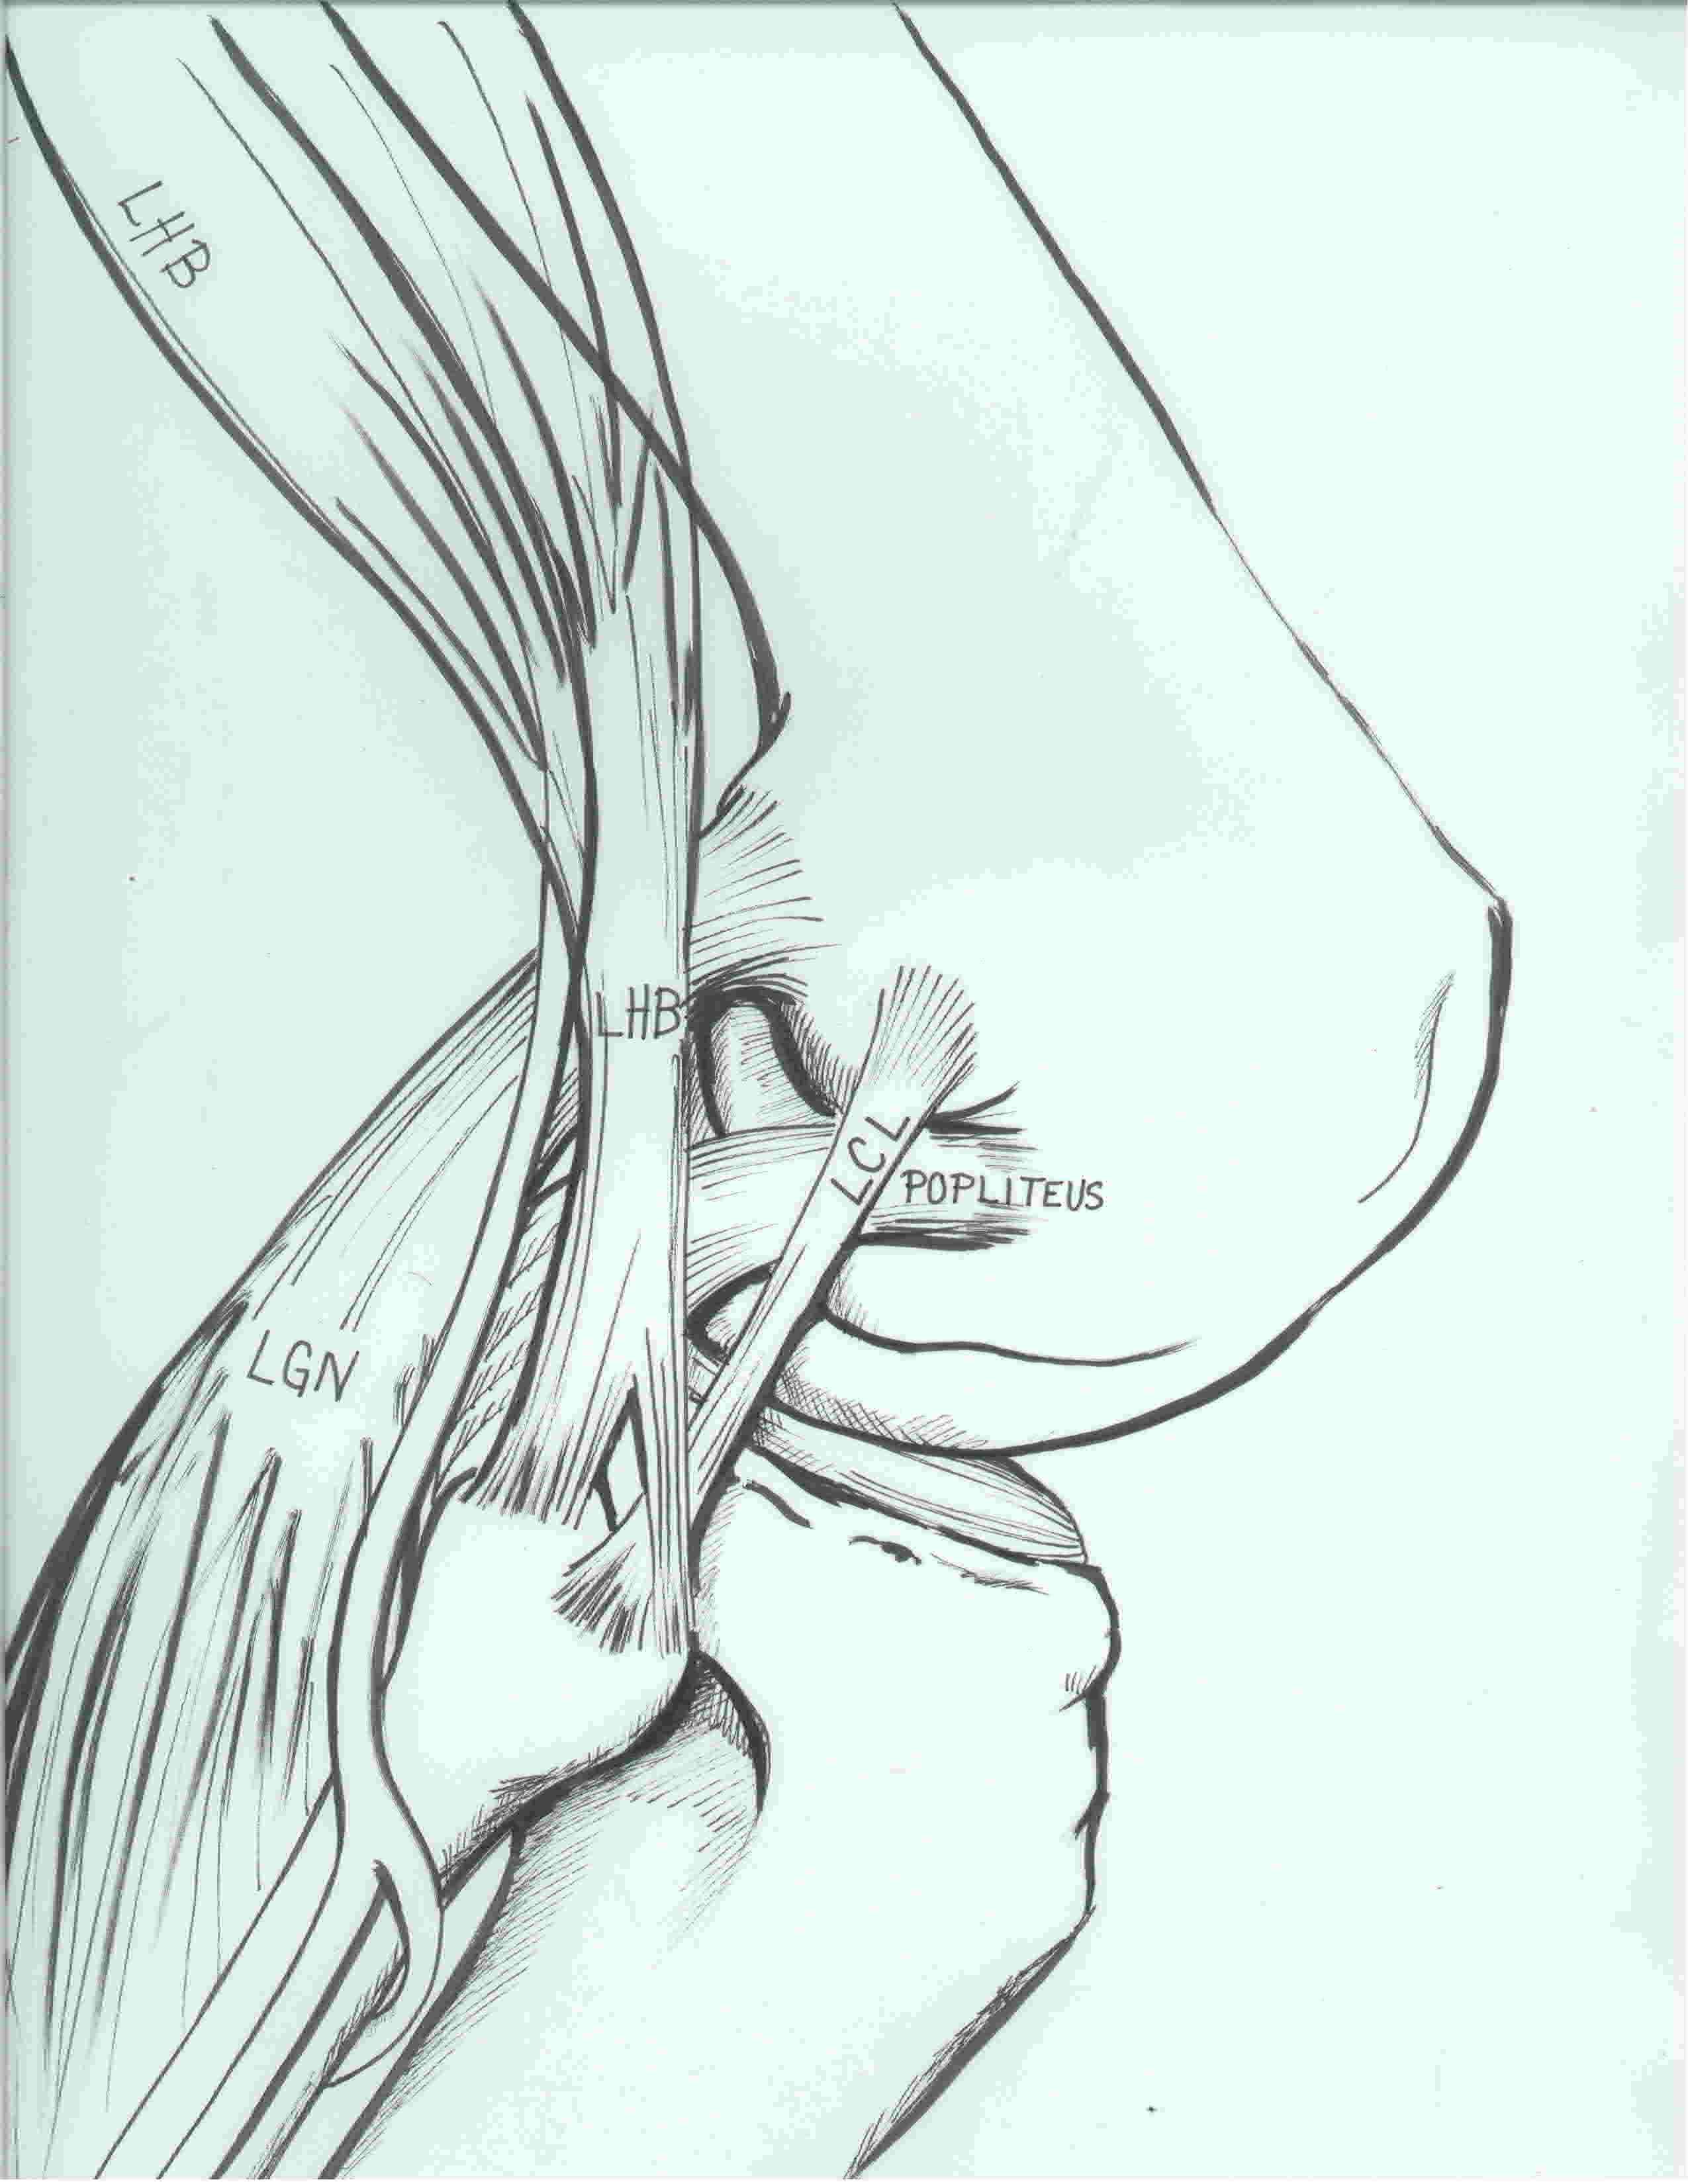

Anatomy

3 primary stabilizers (plus posterolateral capsule)

LCL / Popliteus / Popliteofibular ligament

1. Lateral collateral ligament

2. Popliteus tendon

3. Popliteofibular ligament

ITB, biceps femoris tendon, CPN

Common Peroneal Nerve

Lateral inferior geniculate artery